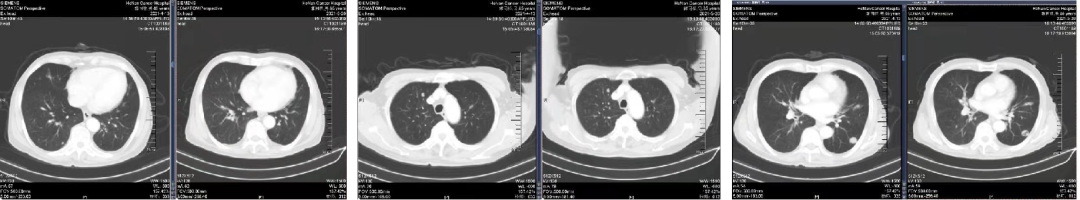

02 初诊病史

诊断:直肠腺癌双肺转移IV期,KRAS 突变型,MSS。高龄,患者及家属无手术意愿,全身系统治疗。

于2021.04.14 始行“曲氟尿苷替匹嘧啶片(TAS-102)+贝伐珠单抗”2周方案治疗至今。

04 疗效评估

患者疾病控制良好,耐受情况好。